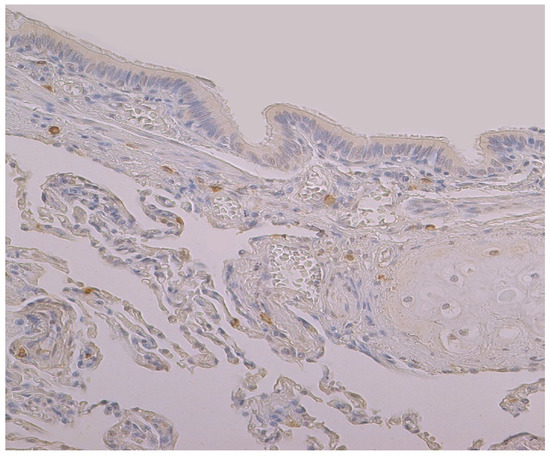

3.1. Tissue Review

3.2. Immunohistochemical (IMH) Data